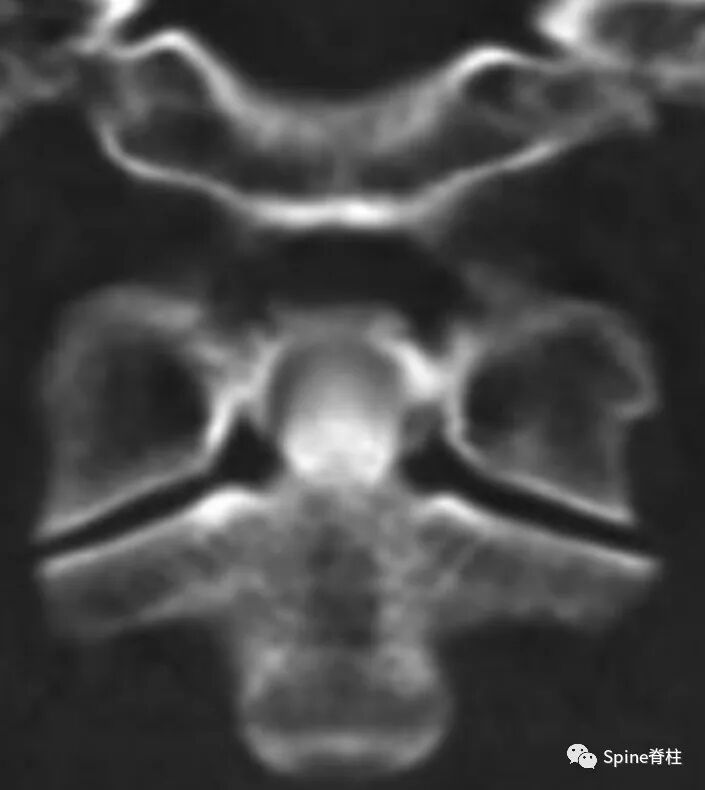

齿状突加冠综合征(Crowned dens syndrome)是指患者以急性颈痛伴随颈椎活动受限就诊,常伴发热,且影像学上表现为齿状突上方或周围出现大小不一、高密度、不规则的钙沉积影,但主要发生在齿状突后侧。因影像学征象犹如齿突戴上了一顶皇冠(如下图),因而得名齿状突加冠综合征,是因钙盐晶体在枢椎齿突周围软组织中沉积形成的。早在1985年,Bouvet等 (Arthritis Rheum, 1985) 首先报道此病。

颈椎CT冠状位重建显示犹如齿突戴上了一顶皇冠故得名齿状突加冠综合征